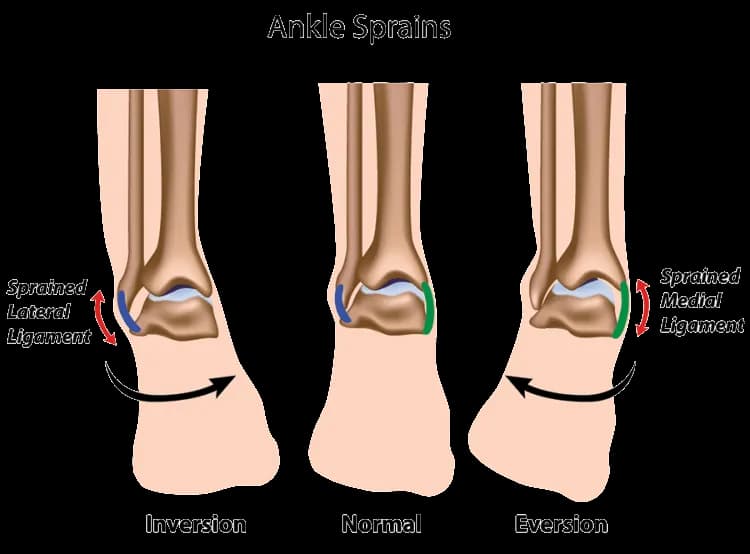

Różnicowanie urazów: jak odróżnić skręcenie od złamania czy zwichnięcia?

Precyzyjna diagnostyka ma ogromne znaczenie w odróżnieniu skręcenia śródstopia od złamania czy zwichnięcia. Każdy z tych urazów wymaga innego podejścia terapeutycznego. Skręcenie to uszkodzenie więzadeł, złamanie to przerwanie ciągłości kości, a zwichnięcie to utrata kontaktu powierzchni stawowych. Badania obrazowe, zwłaszcza TK i MRI, są kluczowe w tej różnicowaniu, pozwalając na postawienie trafnej diagnozy i wdrożenie najskuteczniejszego leczenia.